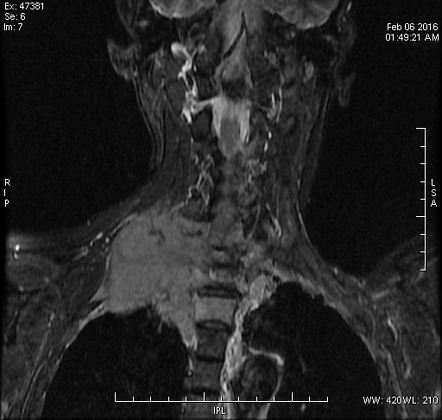

Рентгеновские снимки опухоли Панкоста